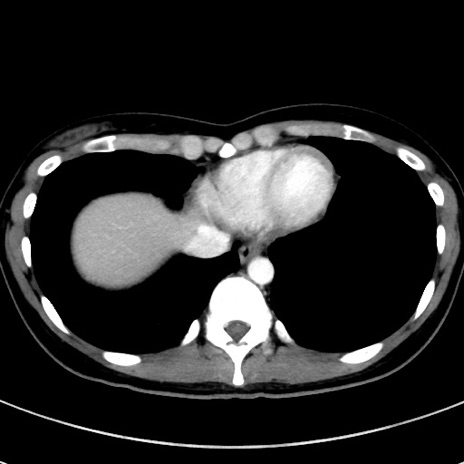

症例17(横断像)

【症例】20歳代女性

【主訴】嘔吐、下腹部痛

【現病歴】昨日夕食後に嘔吐し下腹部痛が出現。本日になっても嘔吐持続し改善しないため来院。

【身体所見】意識清明、BT 37.2℃、BP 108/67mmHg、腹部:平坦、やや硬、下腹部正中から右にかけて圧痛あり、反跳痛軽度あり、tapping pain(+)。

【データ】WBC 13600、CRP 14.94